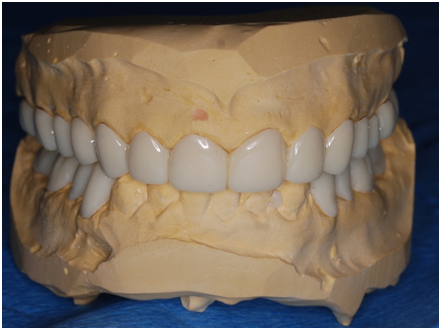

Study casts were poured and mounted according to registered intra occlusal records on which an occlusal splint was made first with a thickness of 1mm; the patient was instructed to wear it for 3 weeks. When the splint thickness was increased into 2mm, the patient complained after 1 week wearing the splint. Accordingly, the thickness of the splint was reduced to 1.5mm. After wearing the splint for two more weeks with no complaints, the splint was then used in the lab to help to construct temporary crowns; the procedure included dividing the splint at the midline to help to mount the cast with the required VDO. One side of the splint was left in place to be used as a guide for the required VD while constructing temporary crowns for the other hand. At the clinic posterior teeth were prepared; first, temporary crowns were constructed following the wax up made in the lab to raise the VDO. The anterior teeth were then prepared and temporary crowns were placed (Figure 8). The patient complained of pain in the lower right premolar area, upon examination tooth # 28 needed root canal treatment.

Figure 7 Study cast front.

Figure 8 Study cast upper.

Figure 9 Study cast lower.

Figure 10 Study cast left.

Figure 11 Study cast right.

Figure 12 Study wax-up.